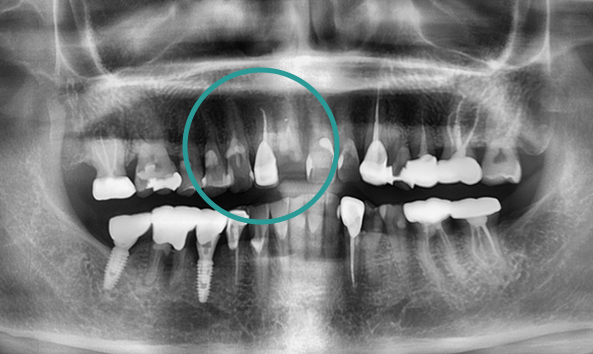

본래 내 치아처럼,

자연스러운 앞니 임플란트

임플란트의 안정성과 심미적인 부분을

모두 고려해야 하는 앞니 임플란트!

어금니보다 공간이 좁고 뼈가 얇기 때문에

정확한 각도와 방향으로 식립 되어야 합니다.

고난도 과정인 앞니 임플란트!

심미와 안정성 모두 약속드립니다.

정밀한 잇몸뼈 상태 확인

앞니 임플란트를 진행하려는 부위에 잇몸뼈가 퇴축되어 있다면 심미적인 문제가 발생할 수 있습니다. 이런 경우, 시술 전 잇몸뼈 이식 수술로 잇몸뼈를 보강한 후 임플란트를 진행해야 합니다.

자연스러운 보철물 제작

치아 보철물에는 다양한 종류가 있습니다. 내부에 메탈이 포함된 보철물과 투명도가 높은 보철물이 있으며, 심미성에 차이가 있는 만큼 환자의 특성과 필요에 맞는 보철물을 선택합니다.

당일 수술 후 임시보철물 완성

앞니는 심미적인 요인과 연결되는 만큼 당일 수술 후 원내에서 바로 임시보철물을 제작하여 일상생활 하실 때 문제 없으시도록 도와드립니다.